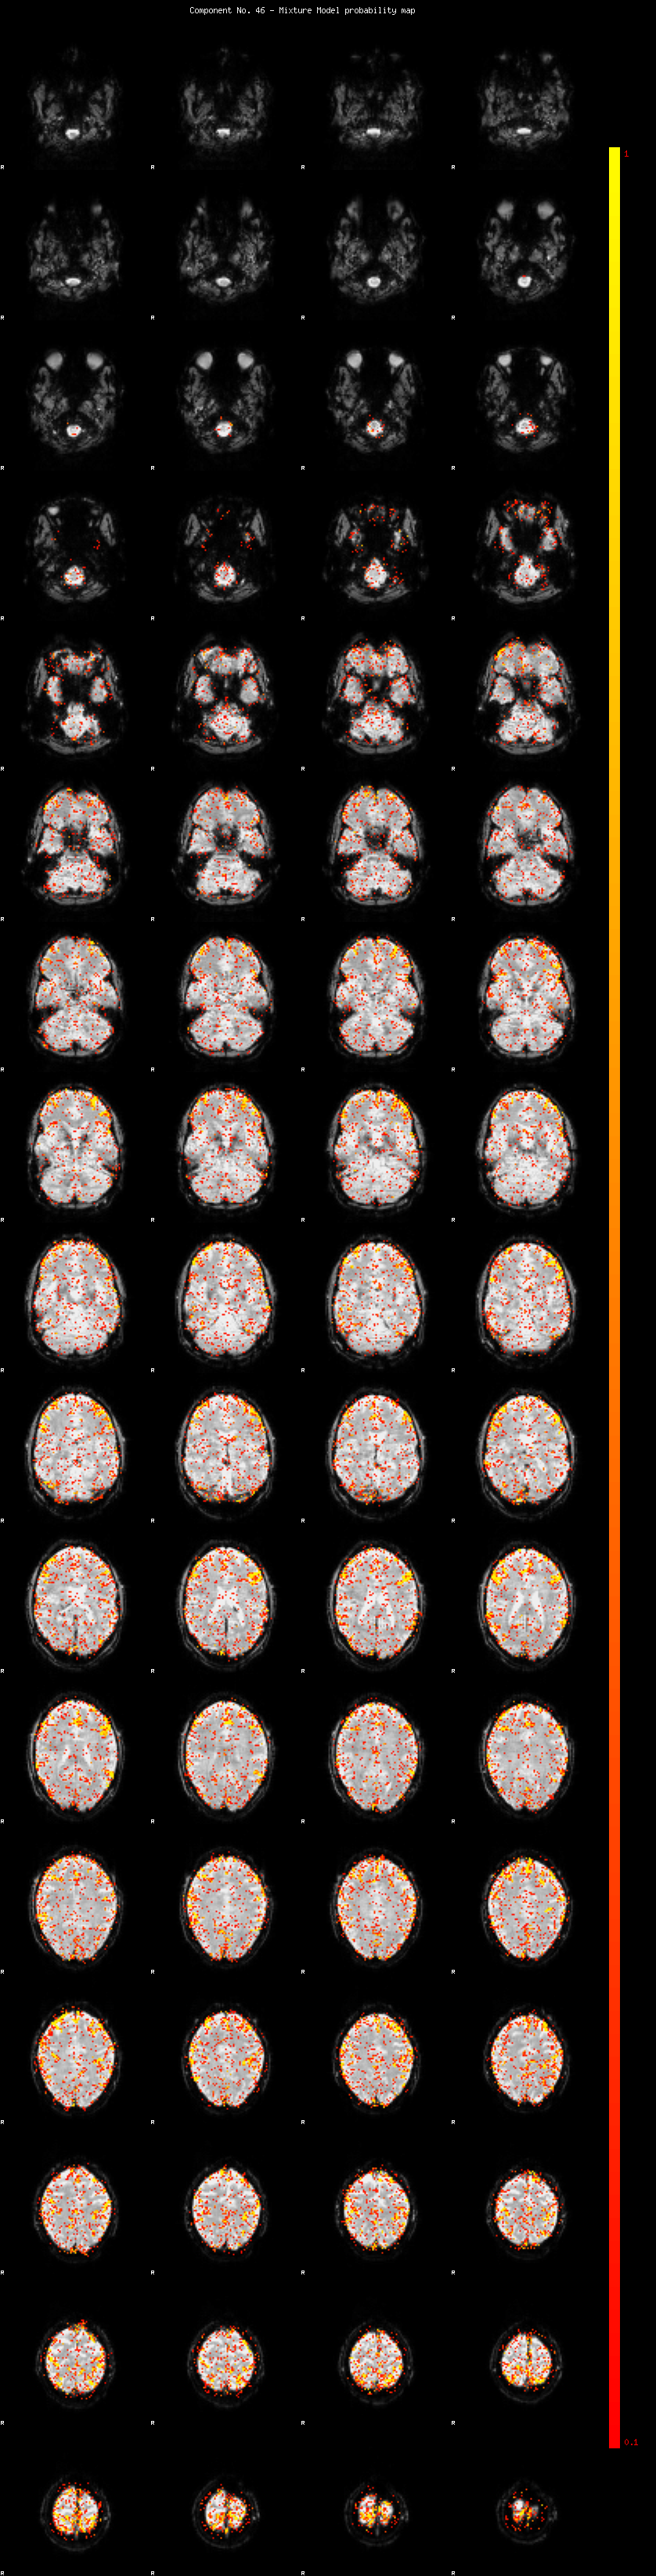

IC_46 Mixture Model fit

Means : -0.000000 2.782412 -2.630413

Vars : 1.000000 2.972189 1.102738

Prop. : 0.930828 0.054406 0.014765

This page produced automatically by MELODIC Version 3.14 - a part of FSL - FMRIB Software Library.